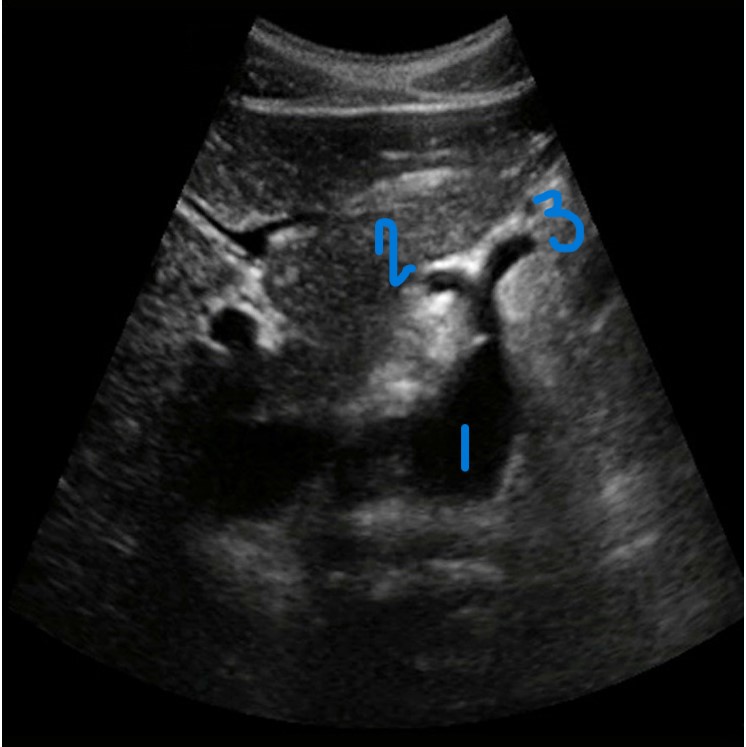

<p>In this sagittal view, what is the structure in this image?</p>

In this sagittal view, what is the structure in this image?

Celiac Trunk